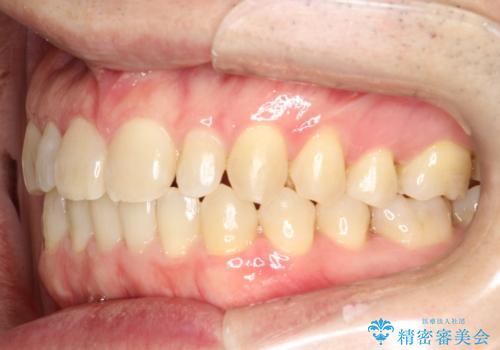

前歯の隙間 インビザラインにて整った歯並びへ

- 前歯の隙間が気になるとのことで来院されました。

インビザラインにて矯正治療を行うこととしました。

下の歯と歯の間にわずかに隙間をつくり、上の前歯の隙間を閉じました。